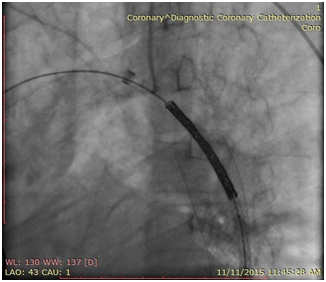

The patient was brought to the endovascular suite and the right groin was prepped. Moderate conscious sedation was administered during the case via a peripheral IV. Access was gained into the right common femoral artery and a 6 French sheath was placed. A pigtail catheter was then placed in the mid descending thoracic aorta and an angiogram was performed demonstrating severe narrowing of the thoracic aorta. The left subclavian artery was not visualized, multiple collateral vessels were seen arising from the mid thoracic aorta. Initial attempts at crossing the stenotic segment with a glide wire and cobra catheter were unsuccessful. The left arm was then prepped and access was gained into the left brachial artery and a 5 Fr sheath was placed. A pigtail catheter was then advanced into the aortic arch and an arch aortogram was performed demonstrating normal branching anatomy with delayed filling of the distal thoracic aorta noted. Simultaneous pressure measurements proximal and distal to the stenosis demonstrated a gradient of 40mmHg. After repeated attempts the stenosis was finally crossed from below using a glide wire and cobra catheter. The glide wire was then exchanged for a 260cm Double Curved Lunderquist wire (Cook Medical). The stenotic segment was predilated with an 8mm by 4cm balloon with resolution of the tight waist seen at 10 atm. The 6 French right groin sheath was then upsized to a 11 Fr sheath. A 20mm diameter by 55mm long Wallstent (Boston Scientific) was then placed across the stenotic segment with the proximal end of the stent positioned just at the origin of the left subclavian artery and the distal end within the descending thoracic aorta past the focal stenotic area. As the stent was unsheathed it migrated distally and opened up distal to the stenotic segment. A 3.9cm long covered balloon expandable Cheatham-platinum (CP) stent (NuMed Inc) was then selected and hand crimped on a 16mm by 6cm long Z-MED (NuMed Inc) balloon. The existing short 11 Fr sheath was replaced for a 70 cm long 11 Fr Mullens sheath which was advanced past the stenotic segment. The balloon mounted stent was then accurately positioned once again, taking care not to cover the left subclavian artery. The sheath was pulled back repeat angiogram performed from the left subclavian artery catheter, and the balloon was carefully inflated. The balloon was deflated and removed. Completion angiogram from the arm approach demonstrated accurate placement of the stent with significant improvement in luminal diameter noted. Repeat simultaneous pressure measurements across the stent demonstrated no residual gradient. The patient was then transferred to the recovery bay were the sheath was removed once the ACT was below 170. The patient had an uneventful post-op recovery and was discharged the following day. At one week clinical follow up, the patient reported significant improvement in symptoms (Figures 1‒4).

Figure 3 Stent positioned across stenotic area and successfully deployed.